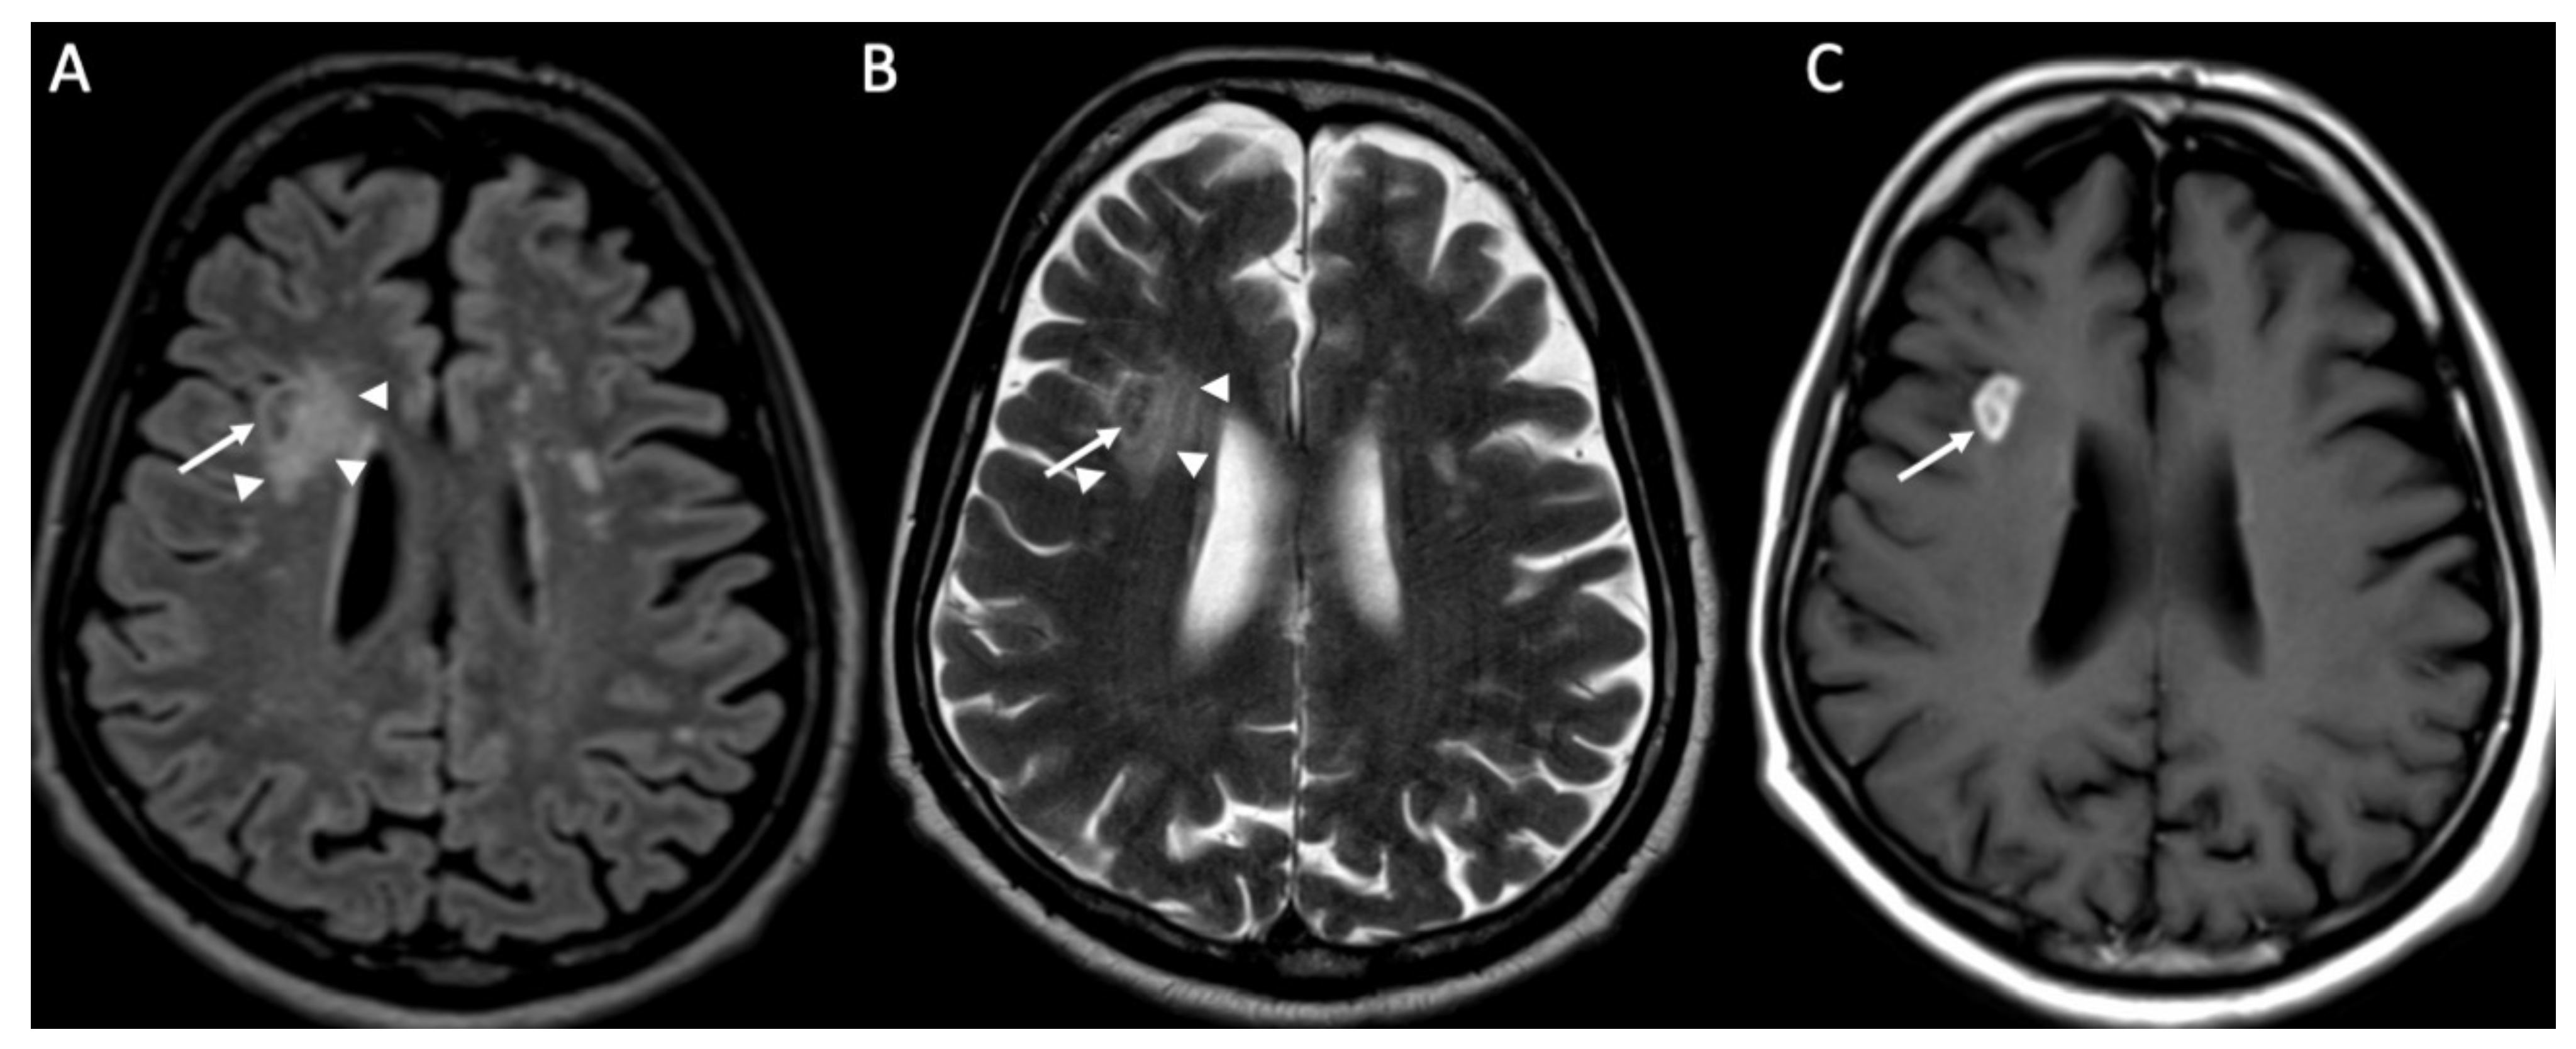

| Cryptococcus Neoformans | • Leptomeningeal enhancement • Cryptococcoma • Gelatinous pseudocysts |

| Candida albicans | • Microabscesses • Vascular lesions |

- Mathur, M.; Johnson, C.E.; Sze, G. Fungal Infections of the Central Nervous System. Neuroimaging Clin. N. Am. 2012, 22, 609–632. [Google Scholar] [CrossRef]